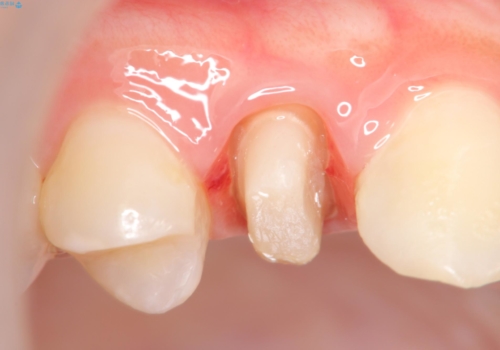

虫歯で歯が折れた セラミック審美修復

- 食事中に急に歯が折れ、周囲の歯も痛みだし治療を希望され来院されました。

ジルコニアクラウンによる咬合機能回復、根管治療を行い歯の痛みをとり長期的な予後の見込める治療を計画します。